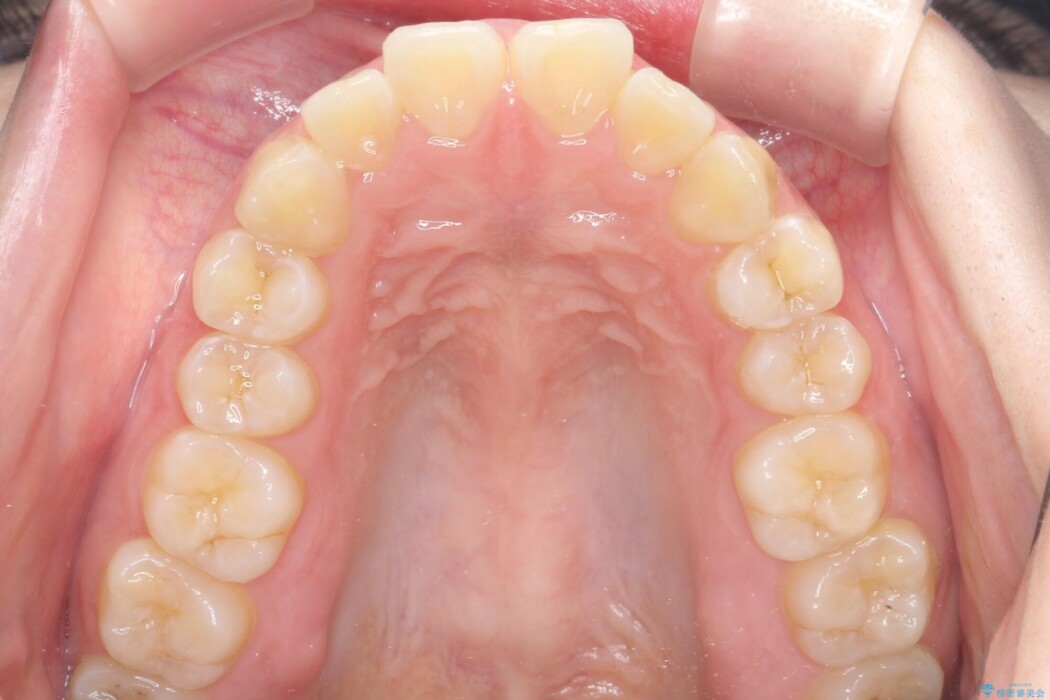

抜歯で得たスペースを活用し、大きく傾いた前歯の角度を修正しながら、ゆっくりと後方へ移動させていきました。

抜歯スペースが閉じるにつれて、唇側の圧迫感が解消され、口元のボリュームが自然に抑えられていきました。

治療後は、口元の突出感が解消され、鼻先から顎先を結ぶ「Eライン」が劇的に変化し「自信を持って笑えるようになった」と大変喜んでいただけました。